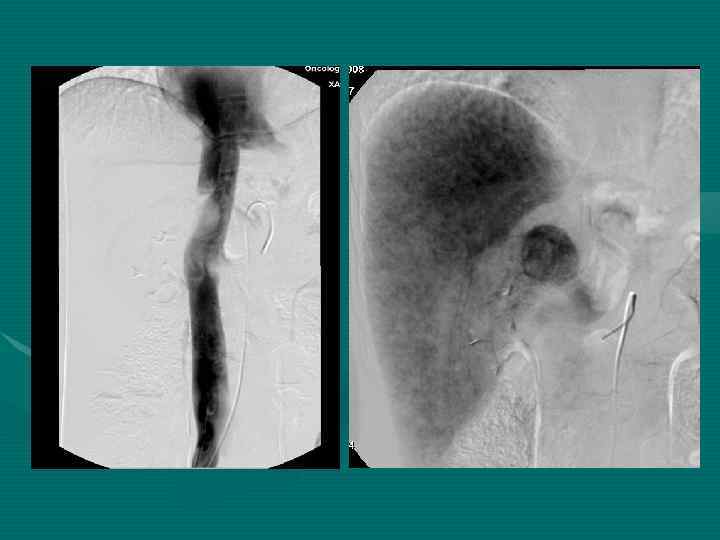

Внутрисосудистое чрескатетерное лечение. 1. Внутриартериальная эмболизация 2. Внутриартериальная химиотерапия 3. Внутриартериальная химиоэмболизация 4. Внутриартериальная радиоэмболизация 5. Внутрипортальная эмболизация 6. Внутрипортальная химиоэмболизация 7. Сочетанное внутрисосудистое чрескатетерное лечение